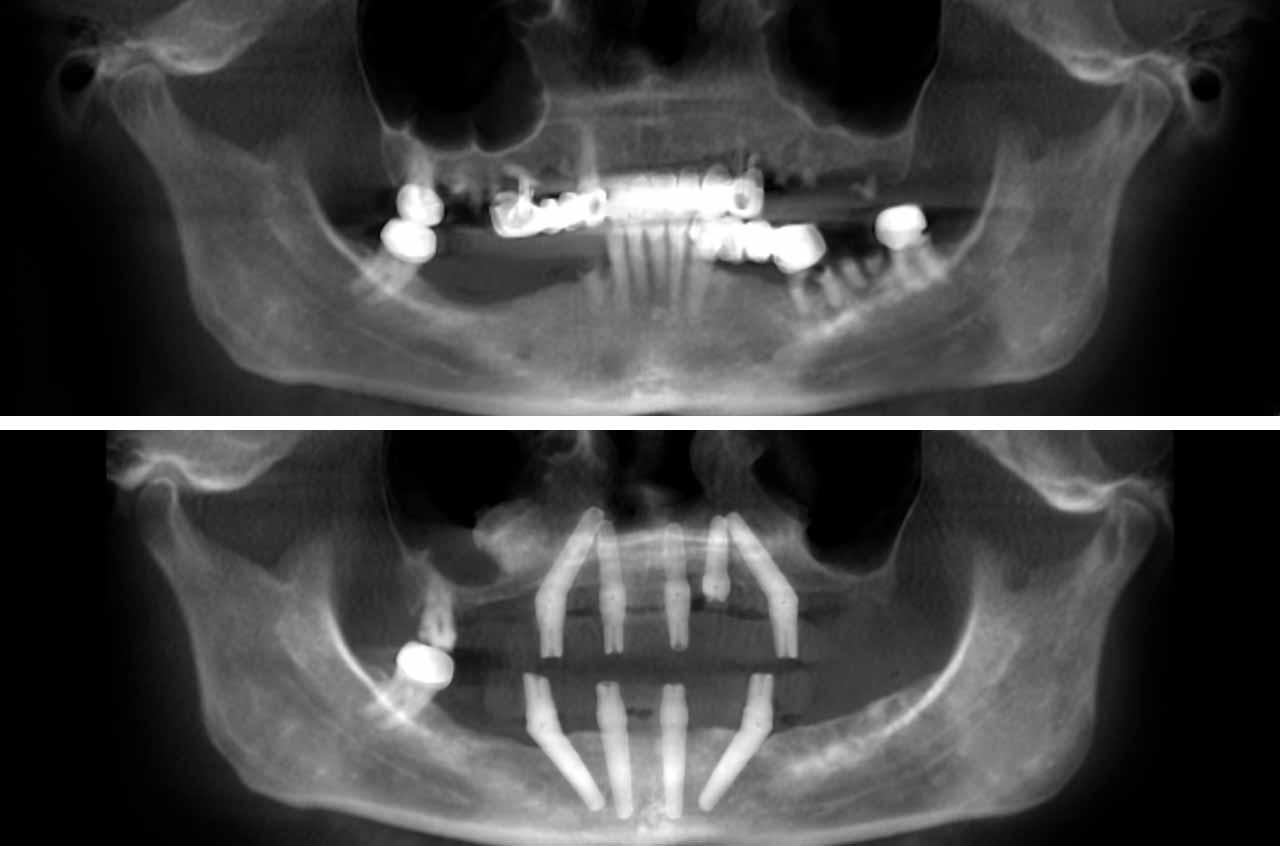

Real before-and-after results from single-tooth implants, All-on-4, All-on-6, and full-arch reconstruction cases.

Each case demonstrates the transformative power of dental implants, from single tooth replacement to full-arch restoration. Our All-on-4 Teeth-In-A-Day technique provides immediate results and long-term stability.

All-on-4 is a revolutionary dental implant technique that uses just four strategically placed implants to support a full arch of replacement teeth. The posterior implants are angled at 30-45 degrees to maximize bone contact and avoid anatomical structures like the maxillary sinus or inferior alveolar nerve. This innovative approach allows for immediate loading with a temporary prosthesis, providing same-day teeth and eliminating the need for lengthy healing periods between procedures.